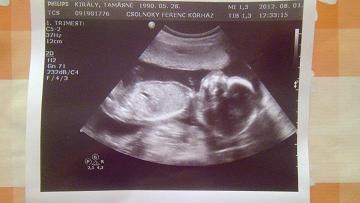

Így látatlanban is tetszik a dokid, ahogy hozzááll a dolgokhoz. Milyen jó, hogy nem kell előbb befeküdnöd!!! Én is mindig azt hallom, hogy az ikreseket berendelik előbb, biztos, ami biztos.